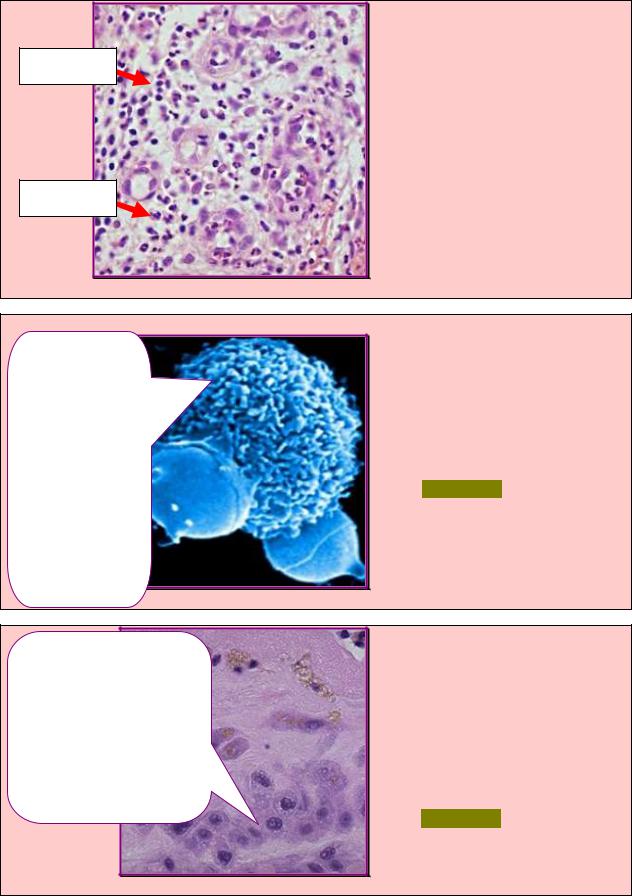

ЗАДАНИЕ 4.33 |

При электронной микроскопии |

макрофага рыхлой соединитель- |

ной ткани выявили характерные |

структуры, |

на |

рис.4.33. |

Укажите |

|

данных структур. |

А. Индукция апоптоза. |

Б. Внутриклеточное |

переваривание. |

В. Миграция и фагоцитоз. |

Г. Распознавание антигена. |

Д. Презентация антигена. |

Рис. 4.33 |

1.Актиновые |

микрофиламенты. |

2.Микротрубочки |

(тубулиновые). |

3.Промежуточные |

филаменты. |

Фаголизосомы |

ЗАДАНИЕ 4.34 |

легкого в макрофаге выявили |

характерные структуры, обозна- |

ченные на рис.4.34. Укажите |

значение данных структур. |

Б. Неспецифический |

фагоцитоз. |

В. Миграция. |

Д. Специфический фагоцитоз. |

Псевдоподии |

Рис. 4.34 |